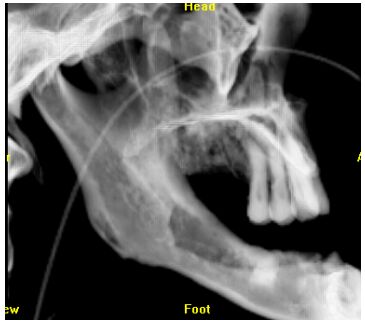

77.一位 22 歲男性患者之顎全景 X 光顯示兩側下顎臼齒下方有周界清晰之放射線透性影像 (圖 A 如箭頭標示),兩側上顎竇亦有放射線不透性影像,手術發現此病變為齒源性角 化囊腫(odontogenic keratocysts);進一步檢查發現中面部有一潰瘍病變(圖 B),腳掌有許多黑色凹點病灶(圖 C),臉部呈現眼距過寬,頭部 X 光可見大腦鐮鈣化(calcification of falx cerebri)(圖 D),胸部 X 光片可見到分歧肋骨(bifid ribs)。根據這些特徵,下列何診斷較可能? (A) Gardner syndrome (B) basal cell nevus syndrome (C) McCune-Albright syndrome (D) Apert syndrome